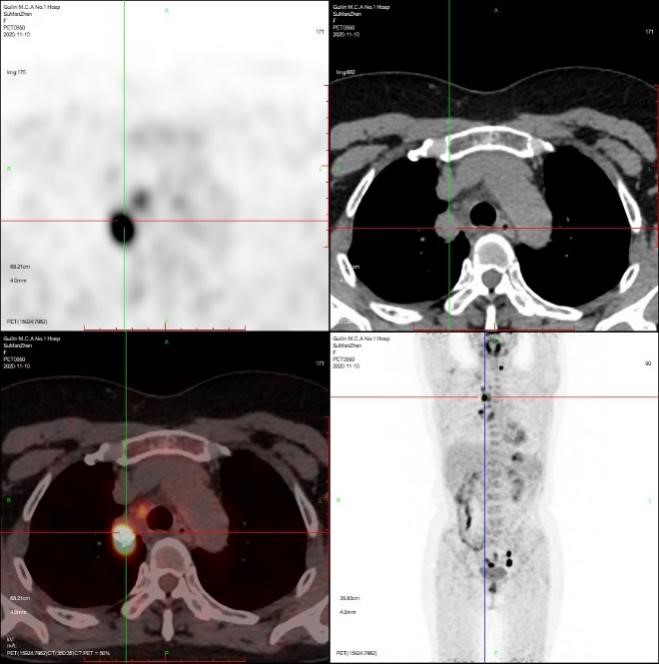

患者粟女士,57岁,既往甲状腺乳头状癌病史6年,近1月来反复咳嗽,当地CT提示肺部占位,为进一步明确诊断,至附属医院核医学科行PET/CT全身检查,提示颈部淋巴结、双肺及子宫内膜多发异常高代谢病灶。

核医学科治疗与影像组医师团队一起认真判读患者PET/CT图像,针对异常摄取病灶,反复评估穿刺进针路径及评估其安全性,技术组全力配合,通过PET/CT精准定位,成功为患者取得了肺及淋巴结组织标本,整个操作过程顺利,手术耗时仅半小时,术中及术后患者无明显不适,术后复查未见血气胸及副损伤。

之后根据PET/CT子宫内膜摄取病灶定位,协助妇科获取了相应部位子宫内膜病理组织。术后完成病理定性、肿瘤组织学亚型分类、分子病理检测。病理提示颈部淋巴结为甲状腺乳头状癌颈部淋巴转移;肺占位为腺泡型肺腺癌(免疫组化支持肺原发来源)。子宫内膜病理提示子宫内膜癌。

患者全身PET/CT图像